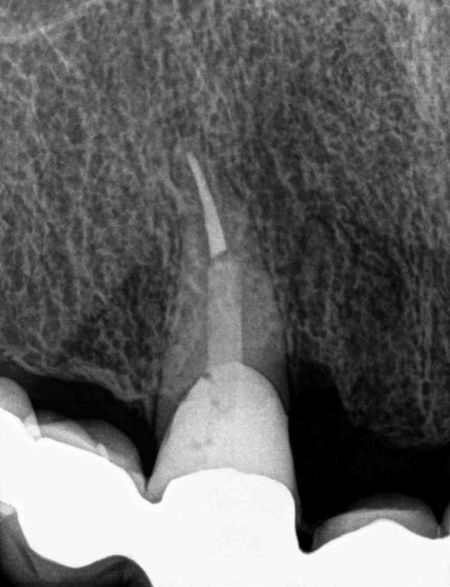

gyökércsúcs rezekció röntgen felvétel

Apicoectomy is an oral surgical procedure during which a part of the tooth’s root, specifically the root apex, is removed along with the inflamed tissues around the root. This procedure can help even when root canal treatment has proven ineffective, thereby saving the tooth in question. Although it involves relatively minor trauma, the procedure still requires a high degree of expertise and careful attention.

As mentioned above, in most cases, apicoectomy is performed when chronic and inflammatory processes complicate our lives, and root canal treatment no longer provides a solution. The procedure may also be considered if a cyst forms around the tooth’s root.

The procedure may also be necessary when the tooth’s canal system is not fully permeable and therefore cannot be cleaned even with specialized instruments. Of course, other problems may arise where the treating dentist determines that root apex removal is the best solution for us.